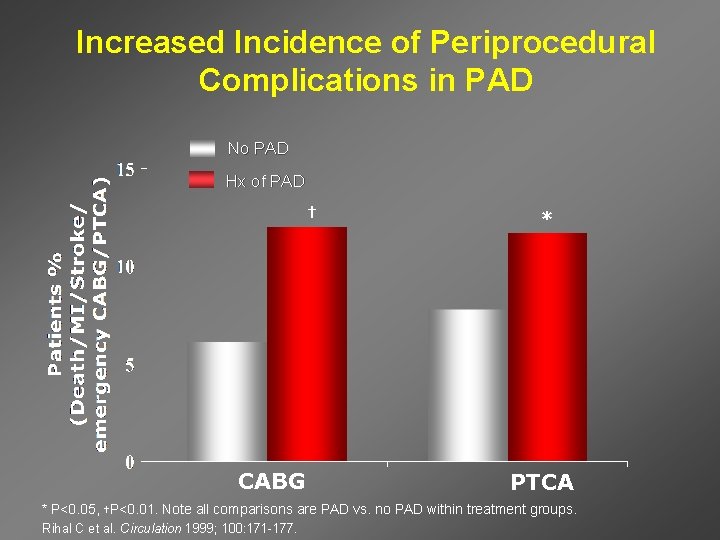

Increased Incidence of Periprocedural Complications in PAD No PAD Hx of PAD † CABG * PTCA * P<0. 05, †P<0. 01. Note all comparisons are PAD vs. no PAD within treatment groups. Rihal C et al. Circulation 1999; 100: 171 -177.